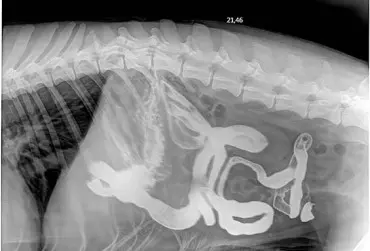

W praktyce weterynaryjnej jest wiele metod diagnostycznych stosowanych w chorobach przewodu pokarmowego. Takie badania jak ultrasonografia, radiografia, endoskopia, tomografia komputerowa, rezonans magnetyczny rozszerzają możliwości diagnostyczne w zrozumieniu chorób jamy brzusznej. Niektórzy pacjenci – poza badaniem klinicznym, wywiadem i badaniem krwi – przechodzą szerszą diagnostykę. Mogą mieć wykonane pojedyncze lub wielokrotne badania obrazowe. Ultrasonografia jest najbardziej popularną metodą diagnostyczną, opiera się na wysokich częstotliwościach ultradźwięków generowanych przez sondę, która poprzez komputer uwidacznia obraz naczyń krwionośnych, tkanek i narządów. Zdjęcie rentgenowskie jamy brzusznej to również typowa procedura medyczna, która pozwala na uwidocznienie kształtów i lokalizacji tkanek, narządów w jamie brzusznej. Główne zastosowanie radiografii to także choroby kości, stawów oraz diagnostyka zmian w klatce piersiowej.